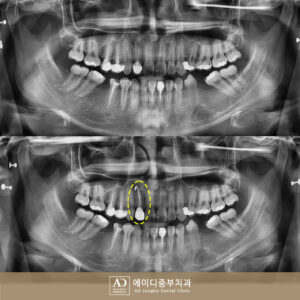

AD중부치과 기존 충전물이 탈락했다면

AD중부치과 기존 충전물이 탈락했다면 충치가 치아의 가장 바깥층인 법랑질에만 국한되어 있고 신경 손상이 없는 초기 단계라면 비교적 간단한 치료로도 충분히 회복이 가능한데요. ​ 이때 대표적으로 시행되는 치료가 바로 아말감 치료와 레진 치료입니다. 아말감이란 은, 주석, 구리 등의 금속과 수은을 혼합한 재료로 만들어진 충전재로 과거에는 보험 적용이 가능하고 강도가 뛰어나 많은 더보기…